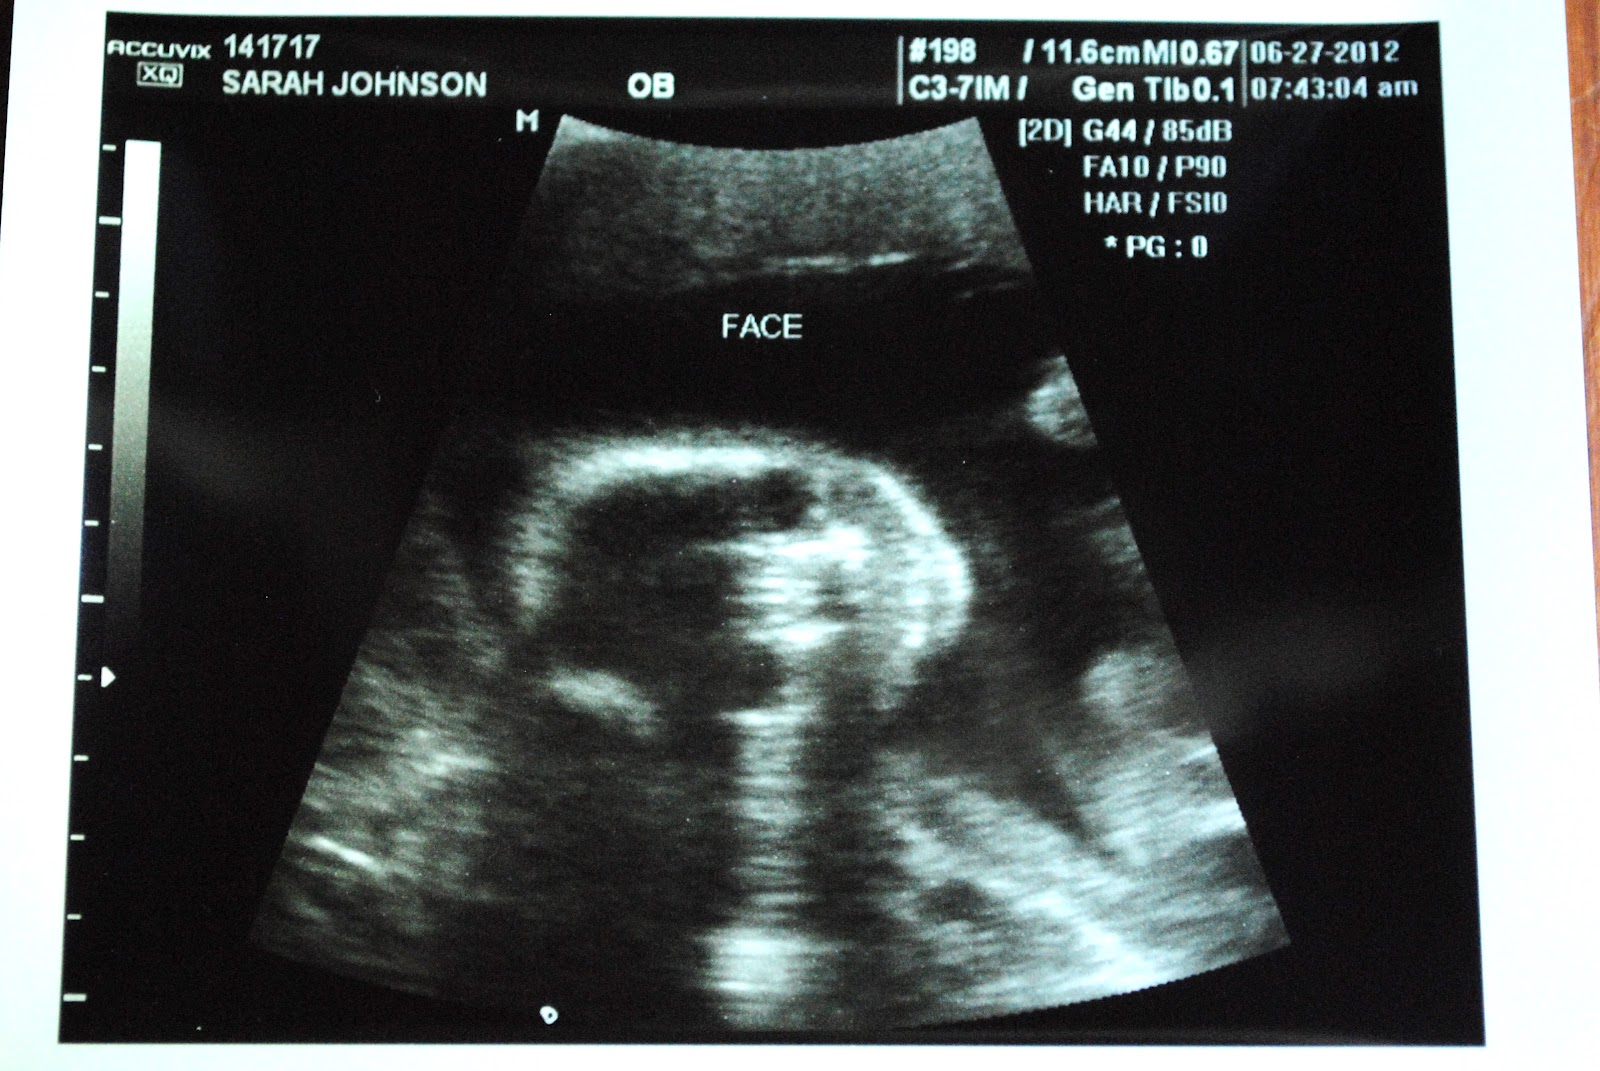

Ultrasound day!

We've had this date on the calendar for quite awhile and knew it would be an exciting day. Ultrasounds are, I think, so amazing! But just last week, we decided that along with checking out our baby's head size, organs, arms, legs, etc. we would also find out the gender this time! Keeping it a surprise with Lainey was awesome and totally worth the wait but we thought we'd try it the other way this time and it was a really fun experience!

We wanted to make it fun and still exciting so I had a card inside an envelope that said, "Baby #2 is a .... boy or girl," and I asked the ultrasound tech to circle whichever one and then seal up the envelope. A few times during the ultrasound, she asked us to look away from the screen which lead me to believe maybe it was a boy, but I also figured since she knew this was our 2nd baby, we probably just knew what we were looking at and looking for and wanted to help us keep it a surprise for a little while. The baby was not super cooperative and she had a really hard time getting a good profile shot and while she wasn't concerned about anything, she also didn't get a good look at the umbilical cord and the belly so she wanted to schedule me to have another ultrasound at my next appointment (score!). Everything else looked great and healthy!

We were so excited! There were a ton of them but here are a few pics of the little mister...